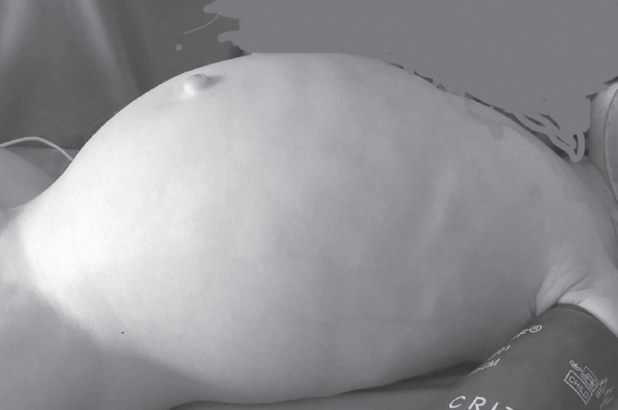

Рис. 2. Вид живота перед операцией

Fig. 2. Abdomen view before the surgery

После выполнения высокого промывания толстой кишки отошло большое количество кашицеобразного стула и газов, живот уменьшился в размерах. Диагноз кишечной непроходимости был исключен. В последующие дни ребенок не срыгивал, питание усваивал, регулярно отходил самостоятельный стул. Выписан на амбулаторное лечение с диагнозом: гипоксически-ишемическое поражение ценральной нервной системы, вегето-висцеральный синдром. На 2-м месяце жизни появилась тенденция к задержке стула, которая нарастала в динамике. Ребенок наблюдался педиатром и ни разу не был осмотрен хирургом. В хирургический стационар поступил в возрасте 10 мес. с клиникой кишечной непроходимости (рис. 2).

Ярким примером недооценки клинической картины служит случай 1. Отсутствие ярких симптомов кишечной непроходимости и эффективность очистительной клизмы позволили уже в первые дни жизни исключить у ребенка хирургическую патологию. Травматичные роды и использование вакуум-экстракции для родоразрешения стали основой для ошибочной интерпретации его состояния. Пациент наблюдался как ребенок с парезом кишечника на фоне черепно-спинальной травмы. На обзорной рентгенограмме брюшной полости расширение толстой кишки на всем протяжении было недооценено. Наличие «светлого» промежутка, характеризующегося отхождением стула, полностью исключило какие-либо подозрения на хирургическую патологию. Ребенок был выписан на амбулаторное лечение педиатром без рекомендации дальнейшего наблюдения хирургом. Следует отметить, что подозрение на кишечную непроходимость, задержку отхождения мекония и расширение толстой кишки при рентгенологическом исследовании у детей первых дней жизни должны наводить неонатолога и тем более хирурга на мысль о возможности болезни Гиршпрунга. В подобных случаях целесообразно выполнять ирригоскопию, которая позволит установить правильный диагноз в большинстве случаев.